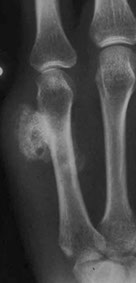

Enchondroma of proximal phalynx

MC form of chondroma (vs juxtacortical chondroma on bone surface); Rare (1% of all) benign bone tumors affecting the hands and feet (65%), and intramedullary metaphysis of long bones (25%) in younger pts (10-30 yo), presenting c pain and swelling

Imaging: well-demarcated purely lytic popcorn-like calcifications (stippled radiolucent defects) and ring-calcifications (formed as part of endochondral ossification) oriented parallel to long axis